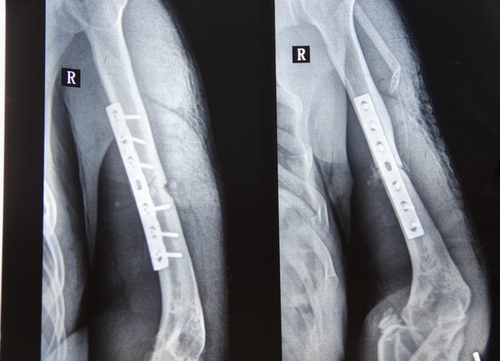

張耀,漢族,出生于1961年10月29日,現(xiàn)住靖邊縣鎮(zhèn)靖鄉(xiāng)蘆西村七組居民。在一九七八年古歷七月三十日,當(dāng)事人張耀在靖邊縣水利局主管和組織的鎮(zhèn)靖人民公社轉(zhuǎn)業(yè)隊(duì),從十個(gè)生產(chǎn)隊(duì)抽調(diào)派人參加鬼門(mén)關(guān)水庫(kù)大壩修建中,因大山崩塌,造成民工周萬(wàn)忠、楊樹(shù)勝兩人死亡,申請(qǐng)人被掩埋,經(jīng)緊急搶救,張耀同志脫離生命危險(xiǎn),但使其右肱骨粉碎性骨折,多處軟組織損傷。當(dāng)時(shí)政府給予住院治療,在家養(yǎng)傷,從此以后也給張耀造成終身的殘疾。

鑒于事故發(fā)生到現(xiàn)在已過(guò)了三十七個(gè)年頭,靖邊縣水利局及有關(guān)單位未向張耀本人做過(guò)任何處理決定,這視為用人單位未作任何處理,同時(shí)證明在當(dāng)時(shí)沒(méi)有與勞動(dòng)者簽訂書(shū)面勞動(dòng)合同的事實(shí),但是以事實(shí)勞動(dòng)關(guān)系認(rèn)定勞動(dòng)關(guān)系確實(shí)存在。事實(shí)勞動(dòng)觀察的成立要件就是勞社部發(fā)[2015]12號(hào)文件通知精神。用人單位招用勞動(dòng)者未訂立勞動(dòng)合同,但同時(shí)具備下列情形的,勞動(dòng)關(guān)系成立。(一)用人單位和勞動(dòng)者符合法律、法規(guī)的主體資格。(二)用人單位依法制定的各項(xiàng)勞動(dòng)規(guī)章制度適用于勞動(dòng)者,勞動(dòng)者受用人單位的勞動(dòng)管理,從事用人單位安排的有報(bào)酬的勞動(dòng)和社會(huì)保障部辦公室《關(guān)于農(nóng)民工適用勞動(dòng)法有關(guān)問(wèn)題的復(fù)函勞社廳函[2013]180號(hào)規(guī)定,凡與用人單位建立勞動(dòng)關(guān)系的農(nóng)民工(包括農(nóng)民輪換工)應(yīng)當(dāng)適用《勞動(dòng)法》,發(fā)生工傷時(shí),應(yīng)適用《企業(yè)職工工傷保險(xiǎn)行政辦法》。2003年4月27日中華人民共和國(guó)國(guó)務(wù)院令第375號(hào)《工傷保險(xiǎn)條例》第十四條(一)款在工作時(shí)間和工作場(chǎng)所內(nèi),因工作原因受到事故傷害的應(yīng)當(dāng)認(rèn)定為工傷。第二十一條,職工發(fā)生工傷經(jīng)治療傷情相對(duì)穩(wěn)定后存在殘疾,影響勞動(dòng)能力的,應(yīng)當(dāng)進(jìn)行勞動(dòng)能力鑒定。張耀同志因殘疾多年疼痛難忍,右胳膊肌肉萎縮,經(jīng)靖邊縣中醫(yī)藥復(fù)查為右面肱骨干粉碎性骨折,內(nèi)固定鋼板保留,榆林市高科法醫(yī)鑒定為右肱骨干陳舊性粉碎性骨折并骨不連影響功能,評(píng)定為八級(jí)傷殘。